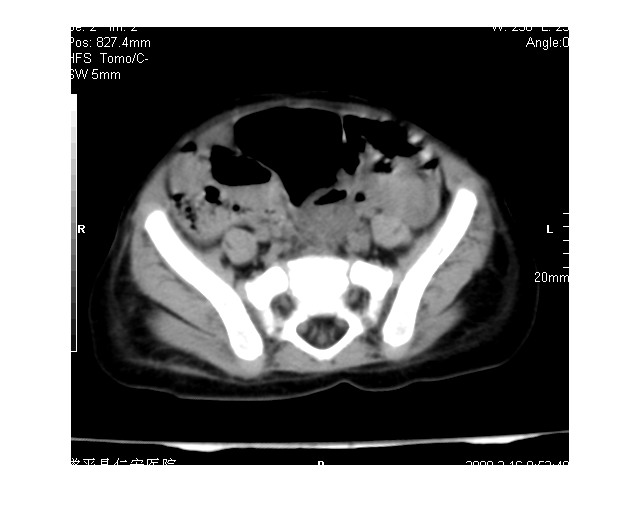

以下是引用lkc8963在2008-3-16 12:49:00的发言:[br]盆底巨大混杂密度肿块,富含多种组织成分包括脂肪/液体/软组织/钙化,边界清楚,向前压迫肠管及膀胱,向后突入骶尾部皮下脂肪层,首先考虑畸胎瘤,诊断时需要与脊柱裂/囊性淋巴管瘤等区别。